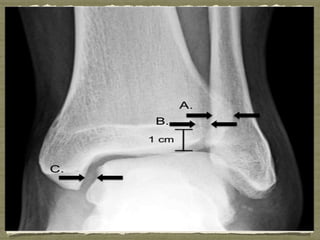

Three radiographic parameters have been defined for the diagnosis

of syndesmotic injury.

The tibiofibular overlap should normally be >6 mm in the

anteroposterior radiograph and >1 mm in the mortise radiograph

as measured 1 cm proximal to the tibial plafond.

Tibiofibular clear space should be <6 mm in both the

anteroposterior and mortise radiographs as measured 1 cm

proximal to the tibial plafond.

Medial clear space should be less than or equal to the clear space

between the talar dome and the tibial plafond

Tibiofibular clear space is the most reliable measure because it is

not affected by the position of the leg relative to the x-ray beam